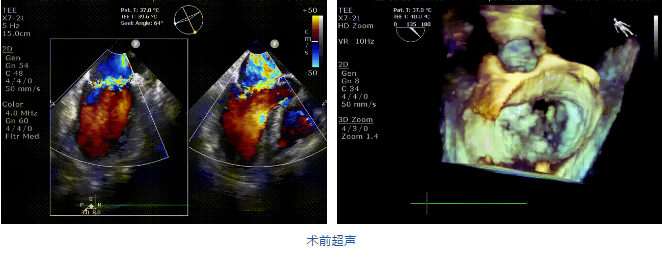

接受治療的是一例二尖瓣重度反流的患者,主訴“突發(fā)間歇性胸悶,氣急6天”。術(shù)前超聲提示:1.二尖瓣脫垂伴重度關(guān)閉不全(瞬時(shí)量30ml);2.左心、右房增大(左房容積110ml,左室容積129ml,右房容積55ml);3.左室收縮功能正常?;颊咴诔浞謽?biāo)準(zhǔn)化藥物治療后(GDMT)仍然癥狀明顯,韓林教授及其團(tuán)隊(duì)唐楊烽教授,以及心超科的周廣為醫(yī)生決定使用我國(guó)創(chuàng)新器械JensClip為患者進(jìn)行二尖瓣緣對(duì)緣修復(fù)手術(shù)。

在阜外醫(yī)院潘湘斌教授團(tuán)隊(duì)的支持下,手術(shù)經(jīng)股靜脈-房間隔入路,采用全身麻醉插管,在TEE和DSA引導(dǎo)下完成房間隔穿刺。置入JensClip瓣膜夾系統(tǒng)后,在左房調(diào)整瓣膜夾的位置和軸向,后進(jìn)入左室,在TEE引導(dǎo)下捕捉二尖瓣前后瓣葉,并關(guān)閉瓣膜夾。經(jīng)TEE反復(fù)確認(rèn)手術(shù)效果后最終鎖定并釋放瓣膜夾。術(shù)后即刻超聲顯示瓣膜夾位置穩(wěn)定,功能良好,二尖瓣反流由術(shù)前4+減少至微量,手術(shù)圓滿成功。